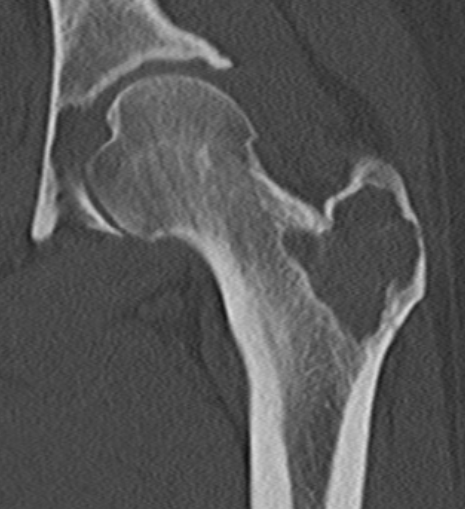

Femoral head osteoblastoma

- 14 cases

- open dislocation and modified trapdoor approach

- no local recurrence

- one case AVN requiring joint replacement